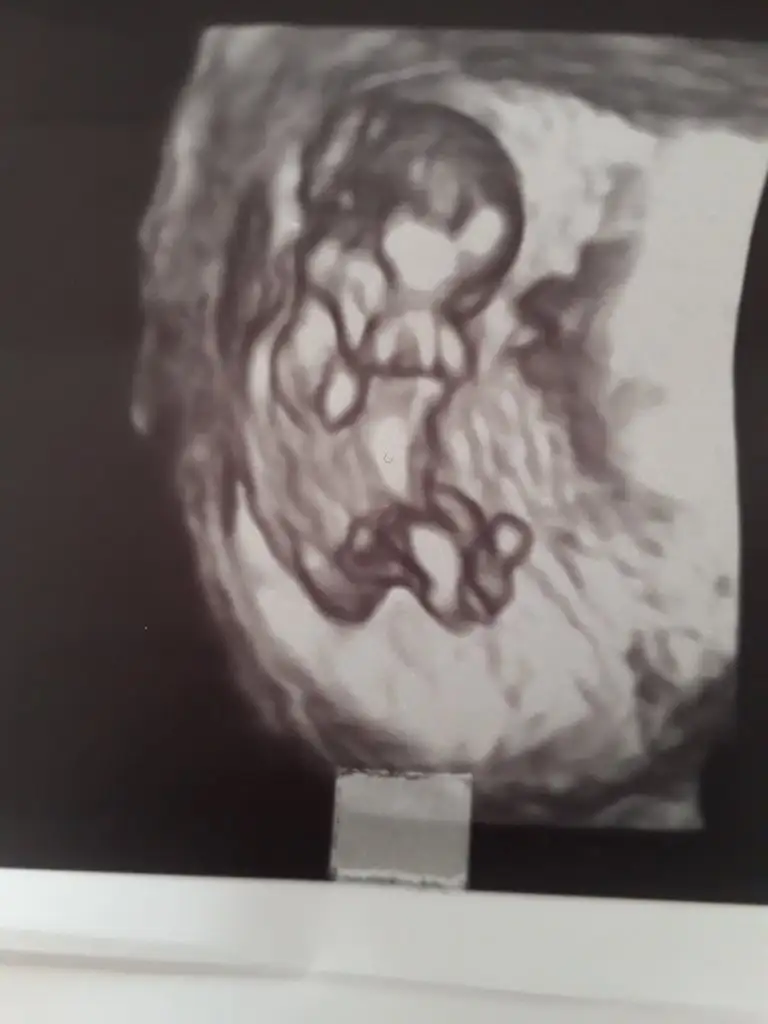

Meraba.12+1 iz cinsiyetini tahmin edebilirmisiniz

Buradaki fotoda 7 haftalıkken.karindan ultrason.bi önceki resimlerde doktor 12 haftalıkken kararsız kaldı.net birşey söyleyemedi.